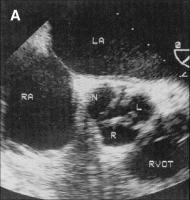

Zerebrovaskuläre Komplikationen nach retrograder Katheterisierung der Aortenklappe bei Patienten mit Aortenklappenstenose - Fact or Fiction?

Journal für Kardiologie - Austrian Journal of Cardiology 2004; 11 (12): 511-514 Volltext (PDF) Summary Abbildungen